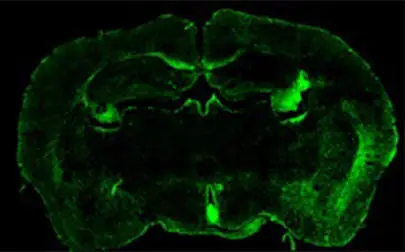

Lethal brain tumour shields itself from immune attack